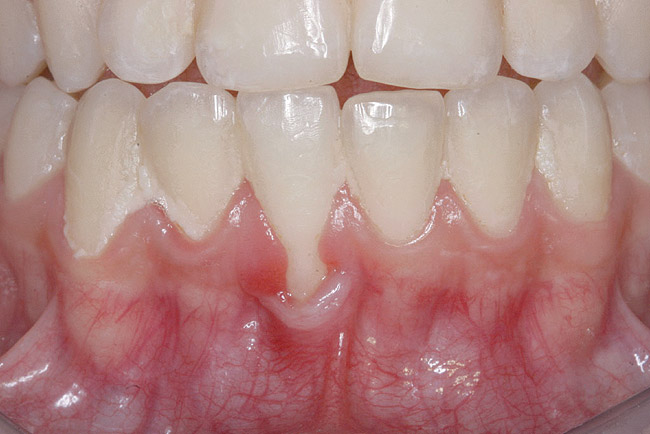

CASE 2 Fig 4. Post-orthodontic Miller Class II recession for which orthodontic treatment was not recommended. Clinical view 3 years after orthodontic treatment, showing relapse in teeth alignment and GR on lower left central incisor.

Figure 4